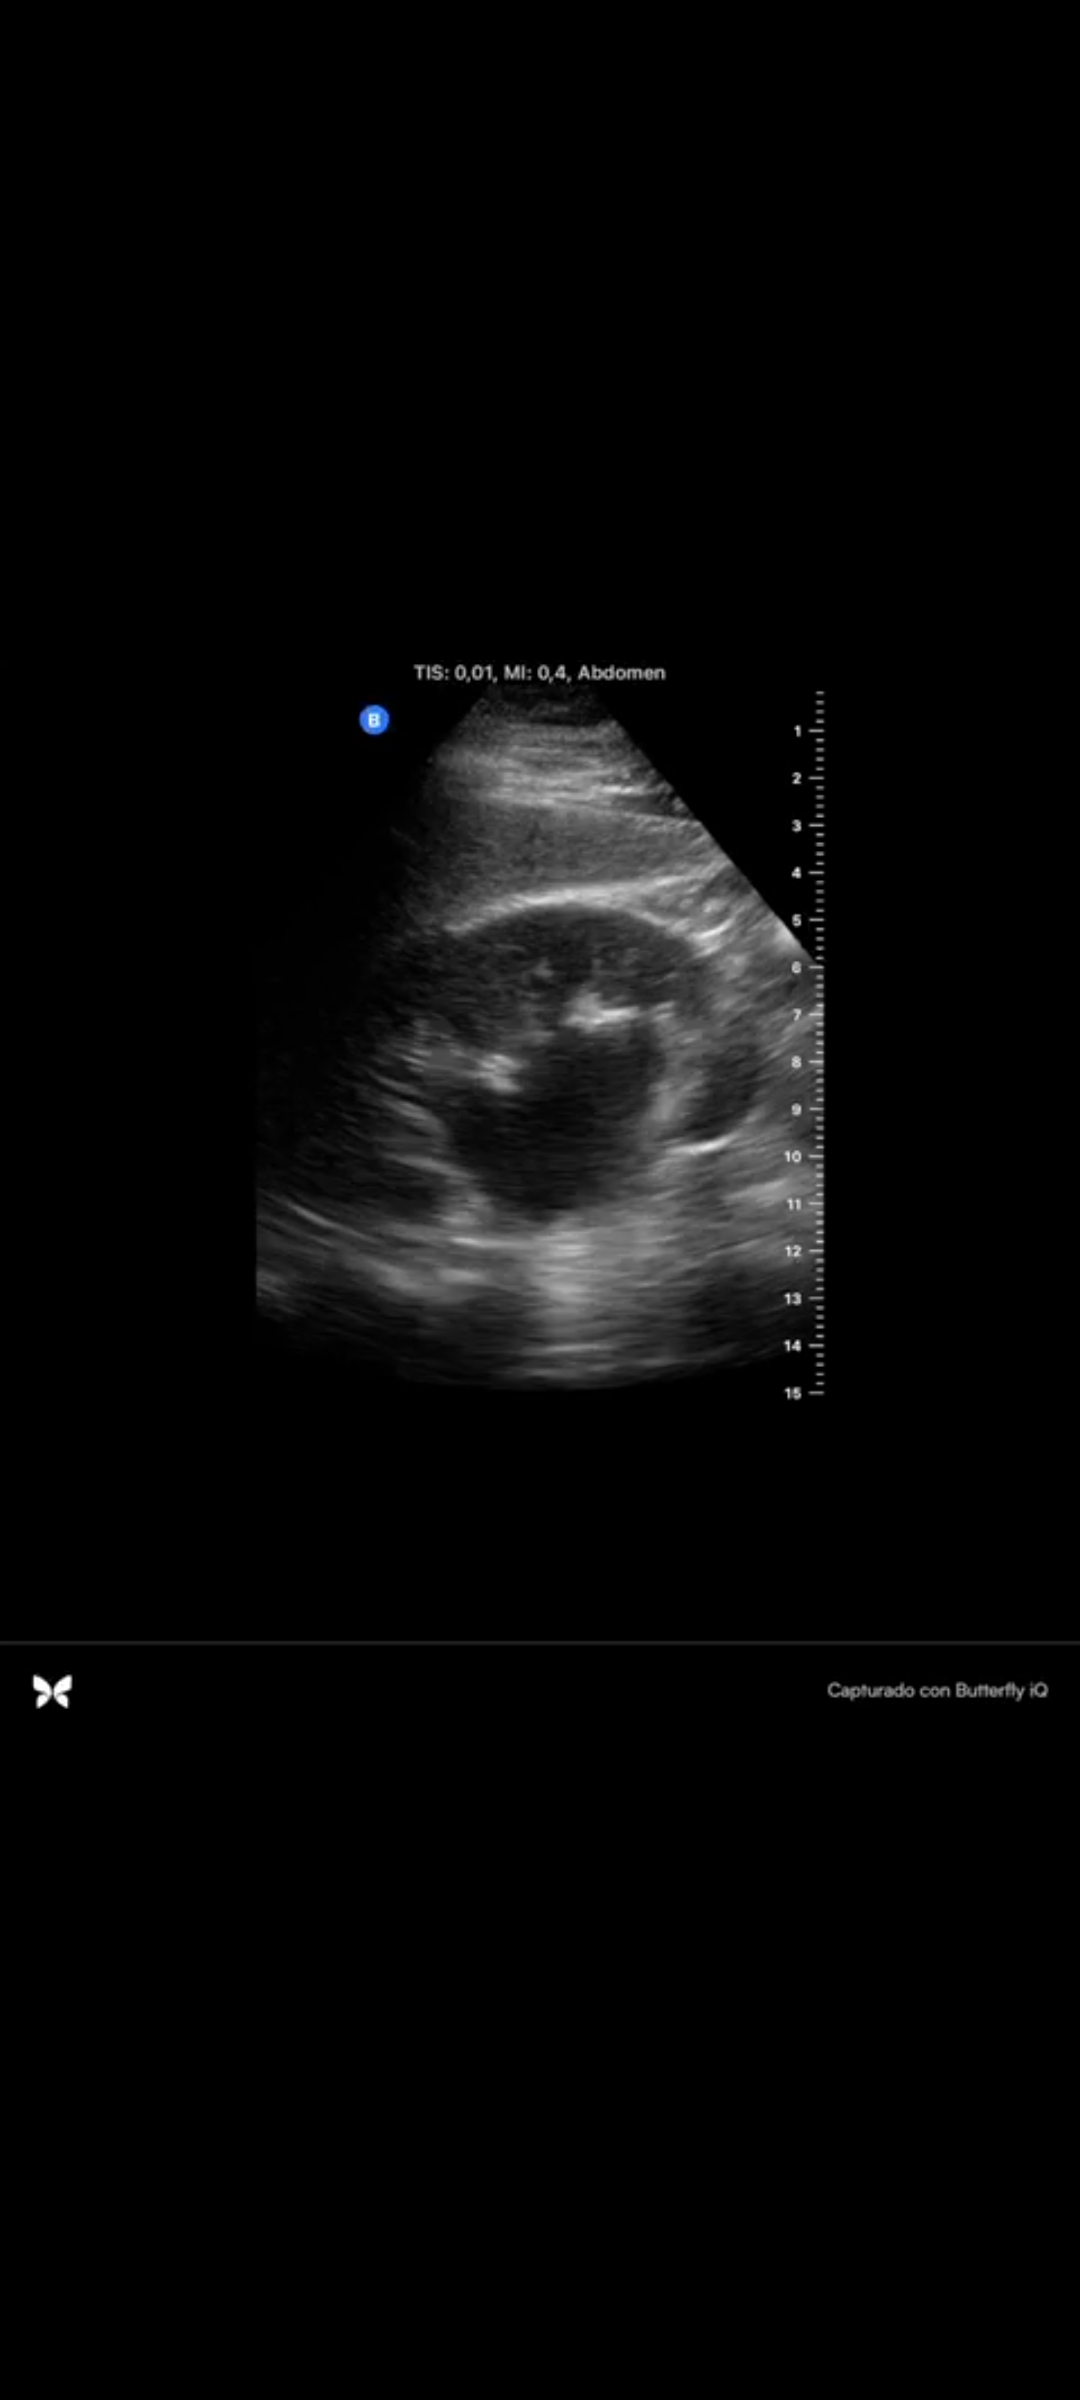

En la ecografía se objetiva hidronefrosis moderada renal derecha sin conseguir visualizarse cálculo renal.

Hidronefrosis en paciente con cólico renal.